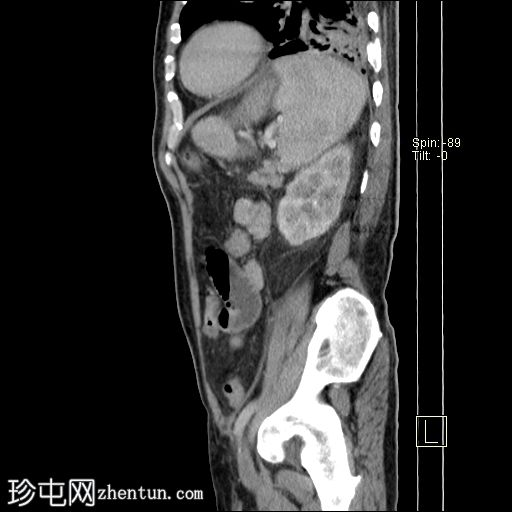

矢状C+门静脉期

脾脏肿大,可见一个边界不清的大型包膜下积液,内有多个大气泡,提示脓肿已延伸至腹腔,导致气腹。

左侧肾旁筋膜反应性增厚,伴有肾周脂肪条带。

左

肺

下叶可见一片实变或肺不张。